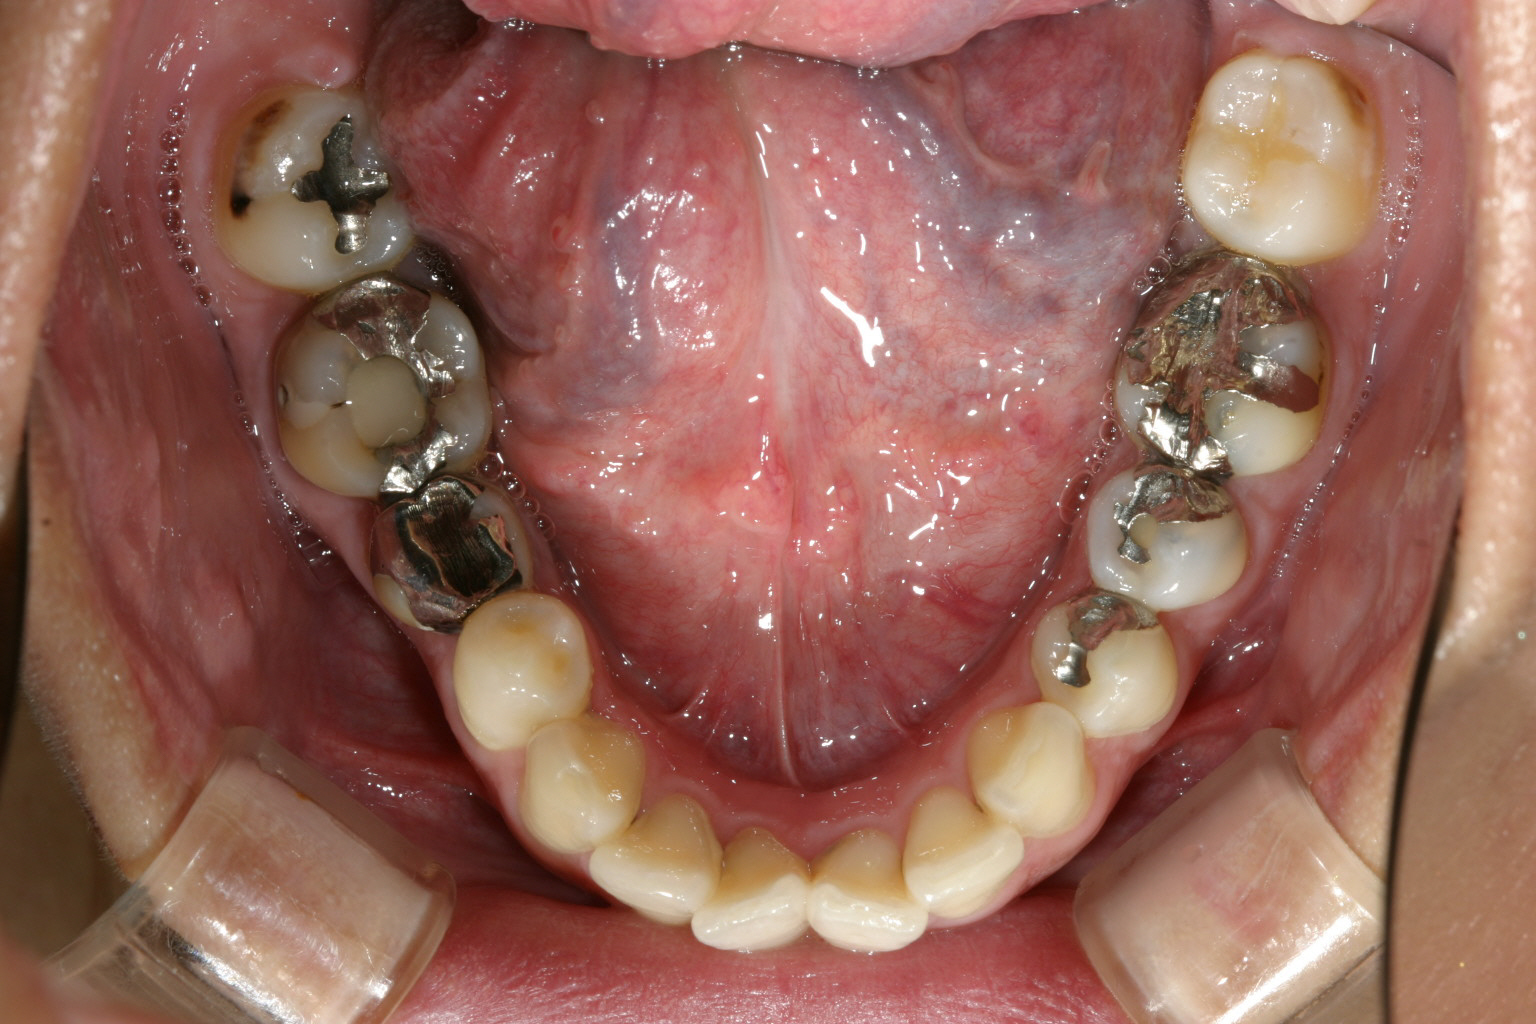

下顎もアーチが狭く前歯部に叢生が見えます。